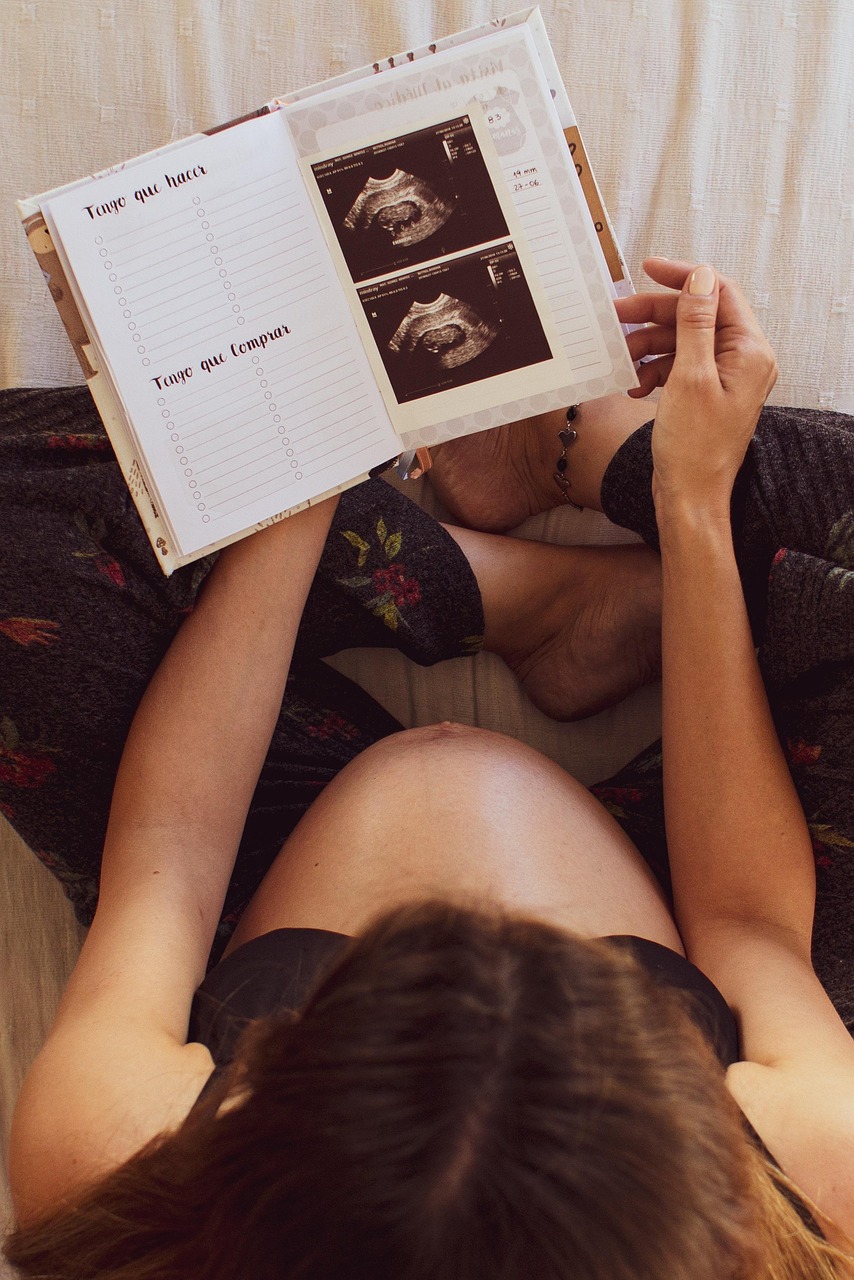

Ultrassom

O ultrassom é um dos exames mais marcantes da gestação. É quando muitas mães têm o primeiro contato visual com o bebê ainda tão pequeno, mas já tão presente. Ao mesmo tempo, é um procedimento técnico,...

Publicado em 06/12/2025